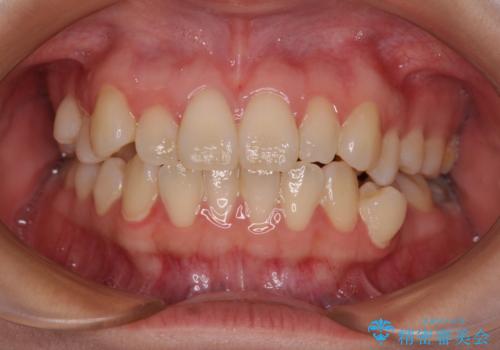

- 20代女性

- 患者様は「歯並び全体のデコボコが気になり、人前で笑うことに抵抗がある」とのことでご来院されました。

診査の結果、上下顎ともに叢生が認められましたが、ワイヤー矯正・マウスピース矯正のいずれでも対応可能な症例でした。